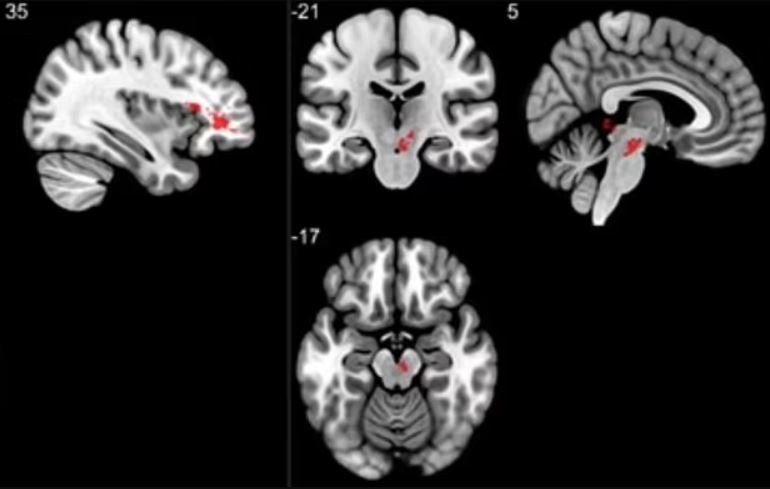

Bilim insanları kırmızıyla işaretlenen bölgelerde değişim meydana geldiğini açıkladı.

Hindistan'da yapılan araştırmayı yürüten Sapna Mishra, "Beyinde değişim olduğu ortaya çıkan bu bölgeler halsizlik, insomnia, anksiyete, depresyon, baş ağrısı ve kavrama yeteneğini ilgilendiren bölgeler" dedi. Beyindeki beyaz maddede değişiklikler oluştuğu kaydedilirken hormonların salınmasında önemli bir rolü olan bölgede de değişiklikler olduğu duyuruldu.